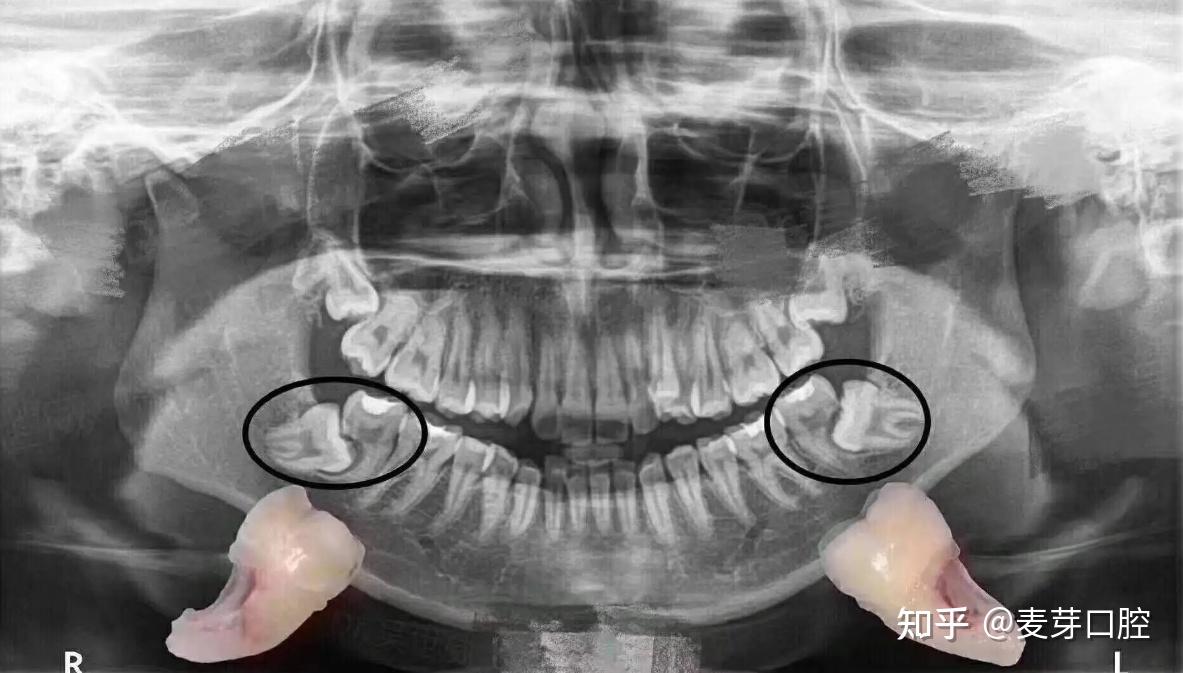

拍牙片辐射大不大?这3类人要看情况! - 知乎

图片尺寸1183x673